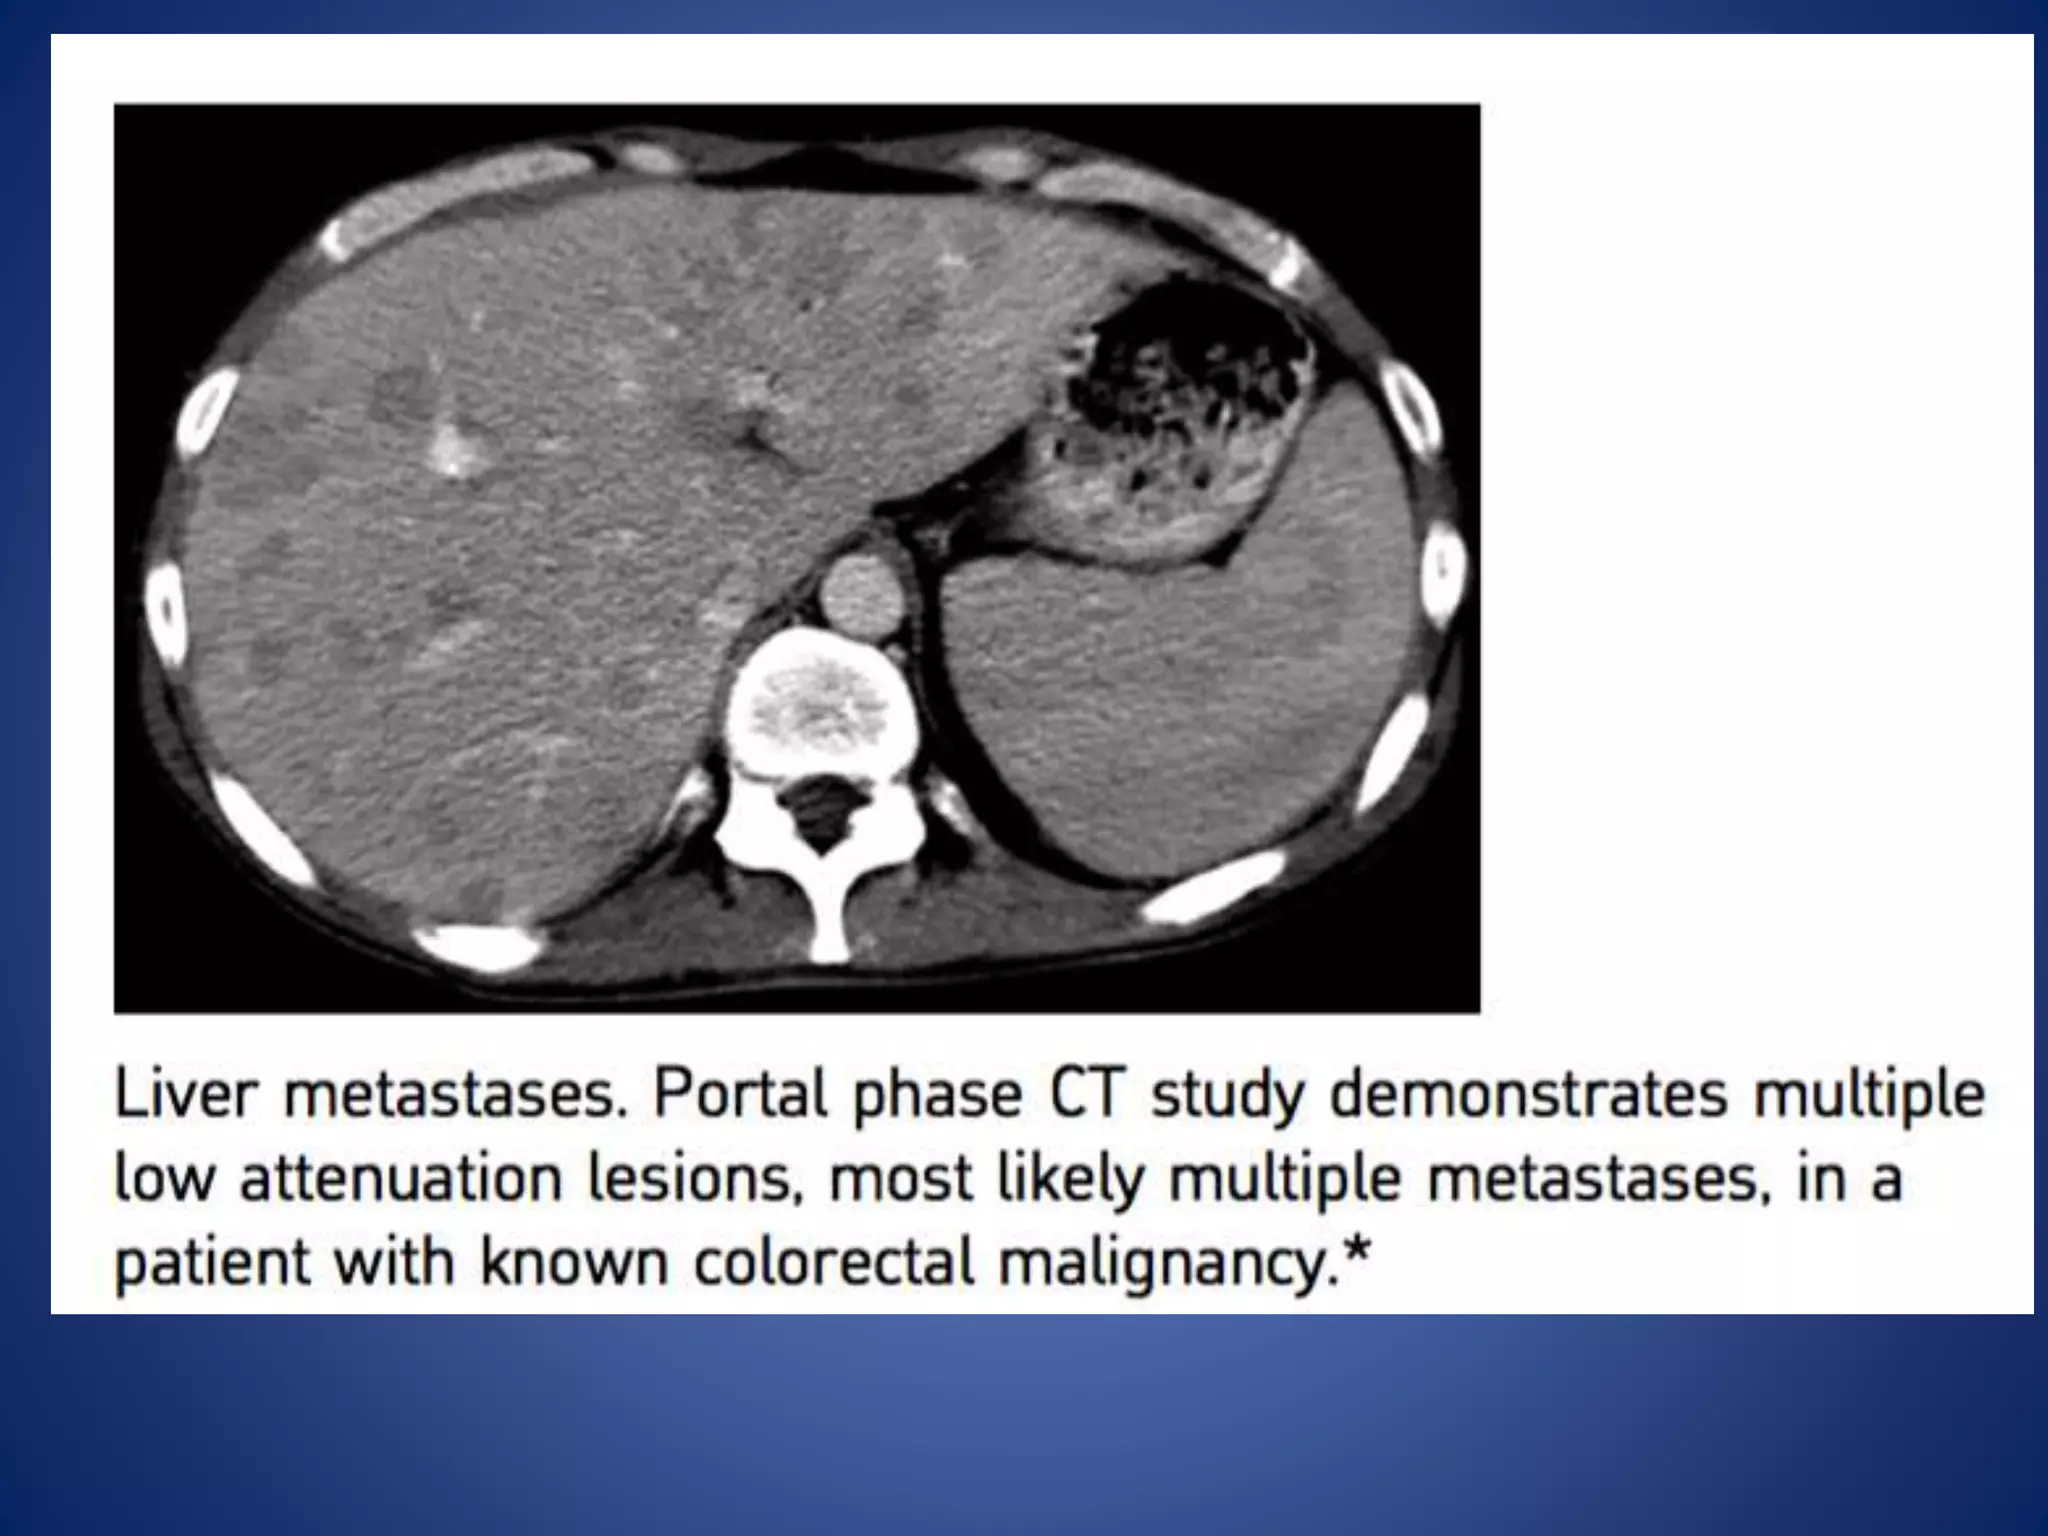

This document discusses various malignant liver lesions including hepatocellular carcinoma (HCC), liver metastases, and angiosarcoma. HCC is the most common primary liver cancer, often occurring in cirrhotic livers, and can appear solitary or multifocal on imaging. Liver metastases commonly spread from gastrointestinal or non-gastrointestinal primary cancers via the hepatic artery or portal vein. Angiosarcoma is a rare malignant vascular liver tumor associated with toxins like polyvinylchloride and arsenic.